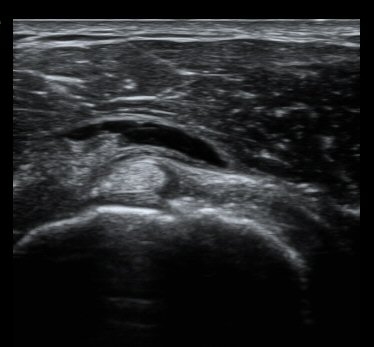

ȸÀü±Ù°³°£°Ý Ⱦ´Ü¸é°Ë»ç¿¡¼­ Á¡¾×³¶³» ¼ö¾×Àú·ù°¡ °üÂûµÈ´Ù(±×¸² 1). ÀÌµÎ¹Ú±Ù°Ç °í¶û¿¡¼­´Â ƯÀÌ ¼Ò°ßÀ» º¸ÀÌÁö ¾Ê´Â´Ù(±×¸² 2). ȸÀü±Ù°³°£°Ý ³»Ãø¿¡¼­ °ß°©ÇϱٰÇÀÇ ÆÄ¿­°ú Á¡¾×³¶³» ¼ö¾×Àú·ù°¡ °üÂûµÈ´Ù(±×¸² 3, 4). ±Ø»ó°Ç Ⱦ´Ü